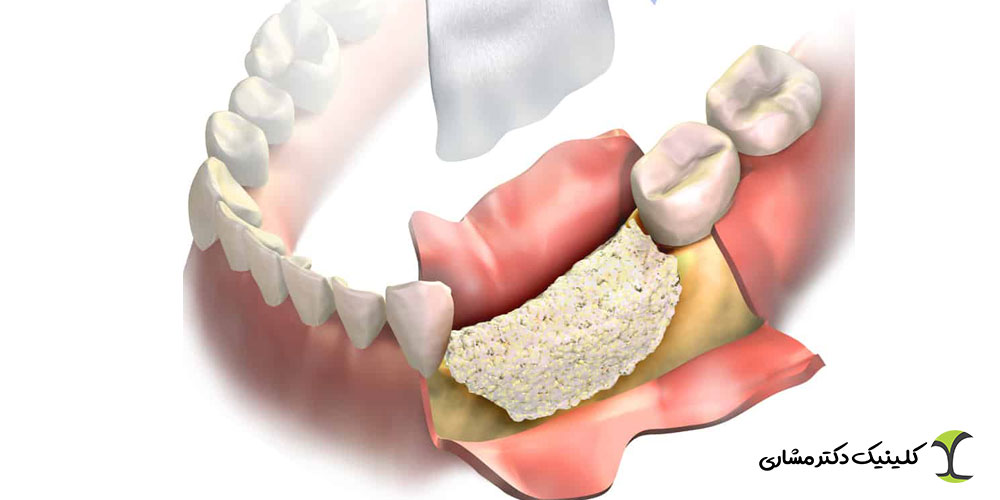

پیوند استخوان یک جراحی تخصصی برای تقویت بافت استخوانی فک است که قبل از کاشت ایمپلنت انجام میشود. زمانی که استخوان دندان به دلیل عوامل مختلف ضعیف، تحلیلرفته یا ناکافی باشد، پزشک با استفاده از مواد استخوانی طبیعی یا مصنوعی، حجم و تراکم فک را افزایش میدهد. داشتن استخوان سالم و محکم برای موفقیت ایمپلنت ضروری است، زیرا پایداری ایمپلنت به مقاومت استخوان اطراف آن وابسته است. پیوند استخوان معمولاً در موارد زیر توصیه میشود:

۱. کمبود تراکم استخوان: وقتی استخوان فک به اندازه کافی محکم نیست و توان نگهداری از ایمپلنت را ندارد، همسطحسازی یا بازسازی استخوان ضروری میشود.

۲. تحلیل استخوان: تحلیل استخوان میتواند بر اثر:

- ضربه یا تروما رخ دهد. در این موارد، پیوند استخوان زمینه را برای درمانهای بعدی، شامل ایمپلنت، فراهم میکند.

هر دو روش سینوس لیفت و پیوند استخوان با هدف تقویت و افزایش حجم استخوان انجام میشوند تا شرایط لازم برای کاشت ایمپلنت فراهم شود. در هر دو تکنیک، از مواد استخوانی طبیعی یا مصنوعی برای بازسازی ناحیه استفاده میشود و نتیجه نهایی، ایجاد پایداری و دوام بیشتر برای ایمپلنت است.